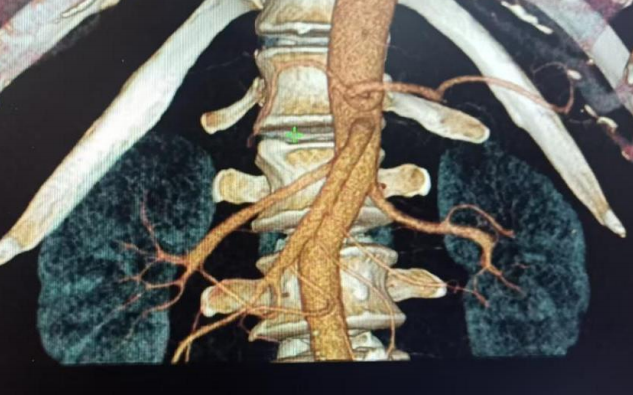

▲双侧肾动脉CT重建